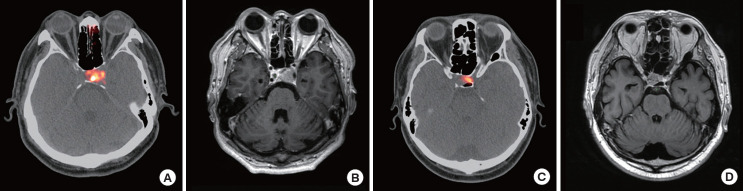

背景:本研究旨在确定68Ga-DOTATOC正电子发射断层扫描/计算机断层扫描(PET/CT)在垂体腺瘤促肾上腺皮质激素(ACTH)分泌中的定位价值。方法:在这项回顾性队列研究中,我们招募了30例ACTH免疫反应阳性的库欣病患者。所有患者在经蝶腺瘤切除术前均行68Ga-DOTATOC PET/CT和垂体磁共振成像(MRI)检查。结果:25例患者的垂体PET/CT显示68Ga-DOTATOC摄取。中位年龄、术前ACTH水平、术前皮质醇和MRI上肿瘤大小具有可比性,与DOTATOC摄取无关。68Ga-DOTATOC PET/CT对腺瘤的定位成功率为77%,与MRI无统计学差异。定位成功组ACTH水平显著高于定位失败组(84.41 pg/mL vs. 37.26 pg/mL, P=0.001)。ACTH水平是68Ga-DOTATOC PET/CT成功定位的显著预测因子(P=0.013)。曲线下面积为0.932,ACTH水平截止值为53.86 pg/mL,确定定位成功。术前ACTH水平高于53.86 pg/mL时,预测腺瘤定位成功的诊断准确率最高(敏感性91.3%;特异性,85.7%)。腺瘤的平均和最大标准化摄取值与术前ACTH水平呈负相关。结论:68Ga-DOTATOC PET/CT显示血浆ACTH水平与促皮质腺瘤的68Ga-DOTATOC摄取呈负相关,是预测促皮质腺瘤成功定位的有利指标。与单纯MRI相比,68Ga-DOTATOC PET/CT不能改善库欣病的肿瘤定位。

Results: Twenty-five patients showed 68Ga-DOTATOC uptake in their pituitary glands on PET/CT. Median age, pre-operative ACTH levels, pre-operative cortisol, and tumor size on MRI were comparable irrespective of DOTATOC uptake. 68Ga-DOTATOC PET/CT showed a 77% success rate for localizing adenomas, which was not statistically different from that of MRI. The ACTH level in the successful localization group was significantly higher than that in the failed group (84.41 pg/mL vs. 37.26 pg/mL, P=0.001). The ACTH level was statistically significant predictor of successful localization using 68Ga-DOTATOC PET/CT (P=0.013). The area under the curve was 0.932 with a cutoff of 53.86 pg/mL for ACTH levels to determine successful localization. Pre-operative ACTH levels above 53.86 pg/mL showed the best diagnostic accuracy in predicting the success of localizing adenomas (sensitivity, 91.3%; specificity, 85.7%). Mean and maximum standardized uptake value of adenoma negatively correlated to pre-operative ACTH level.

Conclusion: Plasma ACTH level is a favorable predictor for the successful localization and negative correlation with 68Ga-DOTATOC uptake of corticotroph adenomas in 68Ga-DOTATOC PET/CT. 68Ga-DOTATOC PET/CT did not improve tumor localization for Cushing's disease compared with MRI alone.